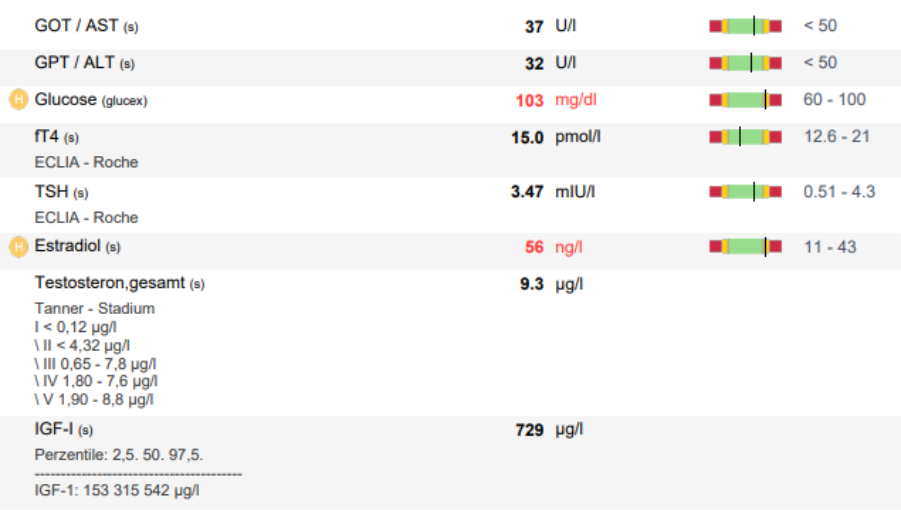

On August 1st I got my first blood test, which included:

-IGF-1

-Free Testosterone

-Estradiol (E2)

-TSH

-fT4

-ALT / AST

Except for Estradiol and glucose, the results were good.

I responded very well to HGH which brought my IGF-1 up to 729 ng/mL.

Until my AI arrived, I lowered my HGH dose to 2 IU and worked on my glucose levels.